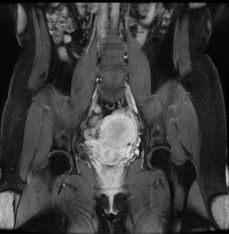

盆腔增強(qiáng)核磁: